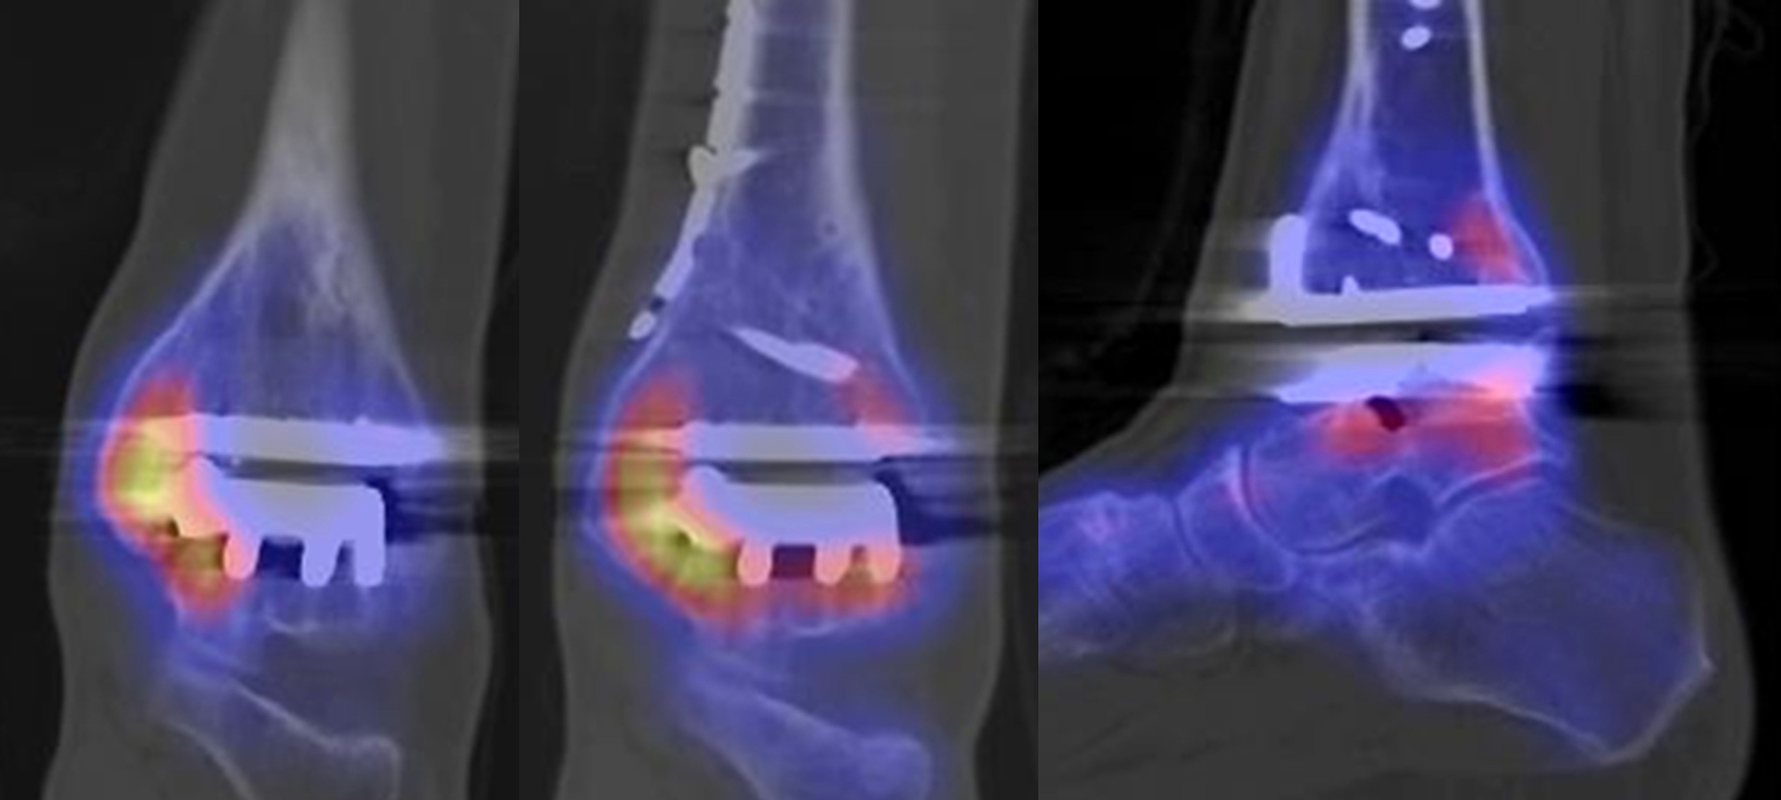

Beispiele für SPECT/CT-Untersuchungen nach OSG-TEP sind in den Abbildungen 6.1. bis 6.3. abgebildet.

Gurbani et al. evaluierten 37 Patienten mit schmerzhaften Sprunggelenkprothesen mit SPECT/CT und korrelierten die Ergebnisse mit klinischen und intraoperativen Befunden. Die SPECT/CT-Ergebnisse korrelierten zu 89,2 % (33/37 Pat.) mit der definitiven Diagnose. 28 Patienten wurden operativ revidiert und der Vergleich der SPECT/CT-Befunde mit den intraoperativen ergab eine Übereinstimmung von 92,9 % (26/28 Pat.). Die SPECT/CT identifizierte in den meisten Fällen aseptische Lockerungen (12/33 Pat.) und Impingement (11/33 Pat.). Seltenere Diagnosen waren Fehlstellungen (4/33 Pat.), Zystenbildungen (2/33 Pat.), subtalare Arthrosen (2/33 Pat.) und Infektionen (2/33 Pat.) 51.

Die Autoren beschreiben einen Fall, der neben einem Fokus am lateralen Malleolus auch eine starke flächige Anreicherung am talaren Prothesen-Knochen-Interface 17 Monate nach TEP-Implantation aufwies, so dass neben dem Verdacht auf ein laterales Impingement auch der Verdacht auf eine Lockerung der talaren Prothesenkomponente geäußert wurde. Intraoperativ bestätigte sich die Lockerung der talaren Prothesenkomponente nicht, sondern nur das laterale Impingement, welches mittels Debridement erfolgreich therapiert wurde 51. Da der Pat. bereits vor der TEP-Implantation eine Triple-Arthrodese erhalten hatte (welche im SPECT/CT unauffällig war), kann eine solche flächige Mehrspeicherung auch als weitgehend asymptomatische Stressreaktion gewertet werden.

Mertens et al. 52 berichten unter Anwendung eines standardisierten Auswerte-Schemas über eine Treffsicherheit von 96 % (Sensitivität 100 %, Spezifität 80 %) des SPECT/CT zur Diagnose der Ursachen für eine schmerzhafte Sprunggelenkprothese (n=24). Der SPECT/CT-Befund führte in 86 % zu einer spezifischen Therapie, welche in 83 % der Fälle zum Therapieerfolg führte.